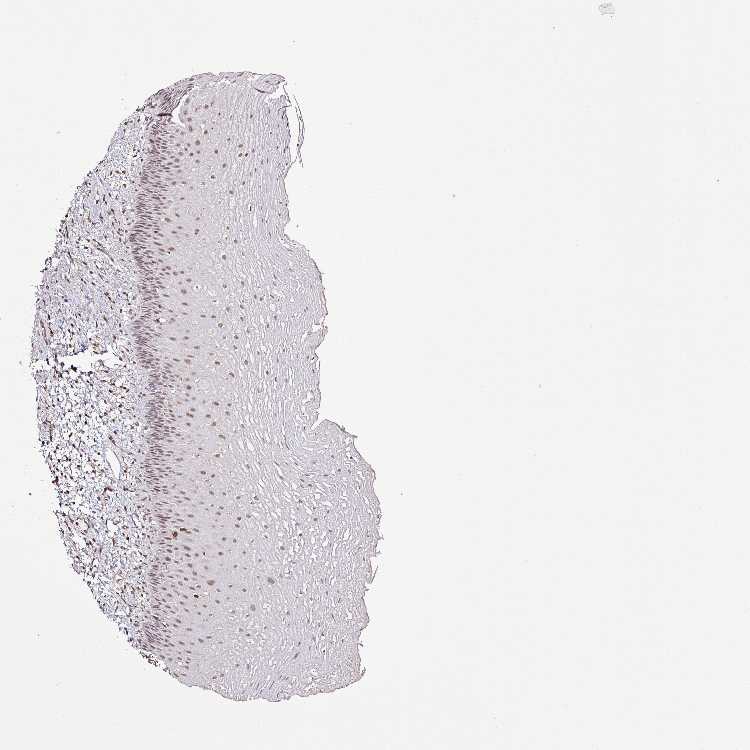

ESOPHAGUS - Antibody stainingi

Antibody staining in the annotated cell types in the current human tissue is reported as not detected, low, medium, or high, based on conventional immunohistochemistry profiling in selected tissues. This score is based on the combination of the staining intensity and fraction of stained cells.

Each image is clickable and will lead to virtual microscopy that enables deeper exploration of all samples and also displays staining intensity scores, fraction scores and subcellular localization as well as patient and tissue information for each sample.

Antibody HPA041120

Squamous epithelial cells Medium